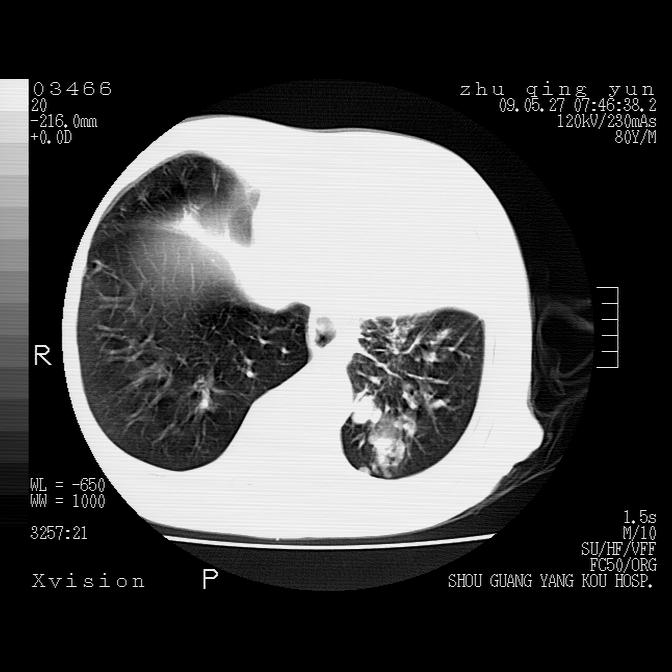

病人男性,年龄80,气喘来院,其他病史不太详细,1月前有过恶心,呕吐,在当地人民医院做过钡餐,诊断胃炎,

1)考虑左肺中央型肺癌并阻塞性肺炎,后下纵隔受侵伴纵隔淋巴结转移。2)双侧少量胸腔积液,胸膜增厚。3)心包积液。

左肺下叶见多发片状及结节状病灶,左肺基底段支气管闭塞,纵隔内见多发淋巴结肿大,纵隔向左侧移位,左侧胸廓变小。应该是左肺下叶中心型肺癌,纵隔淋巴结转移,左侧肺内转移,左肺基底段肺不张,阻塞性肺炎。

1)考虑左肺中央型肺癌并左肺下叶阻塞性肺炎、不张;左胸膜腔积液、心包积液、纵隔淋巴结转移;癌肿累及左心房。2)左心室大。冠状动脉壁钙化斑。

支持以上,左肺肿块应该是周围型吧,考虑左下肺周围型肺癌伴肺内转移,阻塞性肺炎,纵隔淋巴转移,左侧胸膜及心包转移

考虑左下肺中心性肺癌伴阻塞性肺炎,纵隔淋巴转移,左侧胸膜及心包转移。